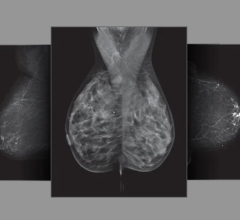

May 13, 2025 — In one of the larger studies of its kind, researchers have identified six breast texture patterns that ...

Despite decades of progress in breast imaging, one challenge continues to test even the most skilled radiologists ...